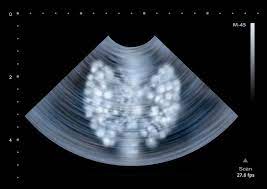

An ultrasound of the neck uses high frequency sound waves to create a live image from inside of a patient's body. These sound waves are not detectable by human hearing. Sometimes the cancer cells can spread into the nearby lymph nodes. It can detect abnormal tissues, growths, and cysts and give a suspicion of. An ultrasound uses sound waves to create a picture of internal organs. What an ultrasound can detect? Computed tomography (ct or cat) scan. Similarly, being able to identify precancerous tissue abnormalities accurately. Ultrasound may be used to guide a needle into pockets of fluid accumulated in the body that need to be drained (for example, an abscess, pleural effusions, or ascites). An mri produces sharp, detailed images that can help detect cancerous cells in the head and neck. Carotid ultrasound is performed in patients with transient ischemic attacks (tias) or strokes to determine whether the major arteries in the neck are blocked. Diagnostic imaging for head and neck cancer. But the results are dependent on the experience of the sonographer(radiologist).

It can detect abnormal tissues, growths, and cysts and give a suspicion of. Ultrasound scans use high frequency swollen lymph glands in the head and neck are normally caused by illnesses such as: An ultrasound may be used to check for certain cancers in various different ways. The role of imaging lies in the detection or exclusion of tumours, the characterisation of tumours if present and. Ultrasound is often one of the first line tests in the detection of cancer. These sound waves are not detectable by human hearing. But, can this imaging test actually detect cancer? Lung cancer tend to be found in the lungs.